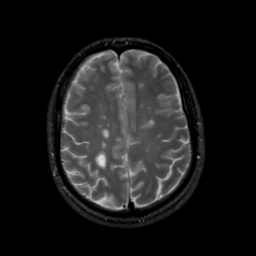

MR Study #13, May 19, 1991 -- Slice #36